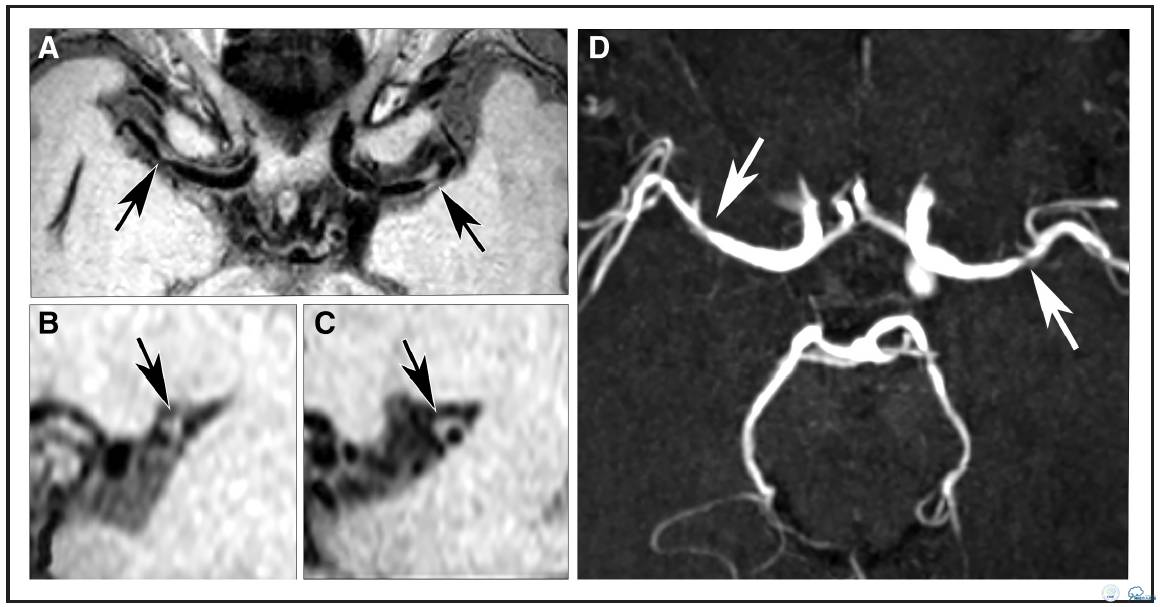

图2:78岁TIA女性患者。A:等中心重建容积采集T1加权快速自旋回波序列成像发现右侧大脑中动脉双侧局部血管壁病变(箭头A),矢状位重建图像(B)右侧大脑中动脉病变(C)显示双侧病变均为偏心性。D:横断面时间飞跃法磁共振血管造影显示对应位置症状性左侧MCA狭窄,无症状性右侧MCA不规则狭窄(箭头D)。

分布、负荷和特征

18例患者(95%)存在颅内血管壁病变,15例患者存在多发病变。评估者间信度很高:组内相关系数为0.71,95%置信区间(0.196-0.920)。评价位置的评估一致性中等偏上,Dice相似系数Dice为0.57。494处受检节段中总共发现57处病变(12%),其中47处(82%)位于前循环(颈内动脉[ICA],n = 18;大脑中动脉[MCA],n = 27,大脑前动脉[ACA], n = 2),10处(18%)位于后循环(基底动脉[BA],n = 3 ;大脑后动脉[PCA],n = 7,见表2及图1)。57处病变中,25处(44%)注射造影后有强化(图2),43处(75%)为偏心性病变,14处(25%)为向心性病变,42处(74%)为局部增厚,15处(26%)为弥散增厚(表3)。在前循环斑块中,偏心病变同局部增厚存相关(图2,图I在线数据补充),向心病变同弥漫性增厚相关(P< 0.001)。19处病变(33%)为症状性病变(MCA病变;1例患者双侧病变),38处病变(67%)为无症状性病变。比较无症状和症状性病变时, 发现偏心性病变和无症状病间存在很大的相关性(P< 0.05)(无症状病变中有32处为偏心病变,占84%;症状性病变中有11处为偏心病变,占58%),但与强化或特定的增厚型式无关。症状性病变没有任何特定的形态特性。此外,MRA上显示正常或不规则的血管壁病变常为无症状病变,而MRA上显示狭窄的或闭塞病变是为症状性病变(P < 0.001;图2)。MRA显示的30处病变中:26处位于前循环,4处位于后循环。此外,MRA上显示的8处病变是在血管壁扫描序列上发现相应病灶。这些病变中,6处为不规则病灶,1处是狭窄病灶(图3),另1处为不规则且闭塞病灶。两处狭窄病灶同时也是症状性病灶。